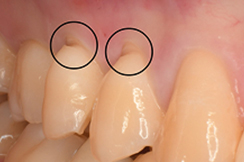

1歯がすり減ってスパッと切れたようにつるつるの面になっている。歯のフチが尖ったりザラついたりしている。

歯がすり減る

2り減った面の真ん中に行くにつれてさらに茶色のへこみができている(エナメル質がすべて摩耗し、芯部の象牙質が見えてしまっている)

茶色のへこみができる